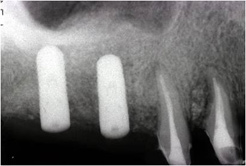

造成骨の成熟を数ヶ月間待ちます。

骨造成を確認後インプラント埋込。

数ヶ月後上部構造を作成して治療終了。